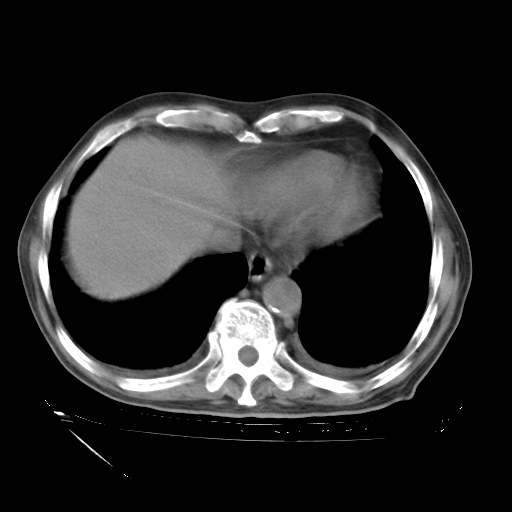

经过24天治疗,岳父的病情基本稳定。生活基本可以自理,可以下床活动。呼吸困难早已消失。体温基本正常。

主要治疗甲强龙80mg×14天,60mg×10天;同时抗结核(异烟肼+利福平+乙胺丁醇)。环磷酰胺0.1 tid 10天。

特别感谢胡教授、高管、桃子版主给出关键的治疗建议。桃版把所有肺部影像和全部临床资料请所在医院呼吸科、感染病科、结核科、临床免疫科专家会诊。临床免疫科专家制定了完整的治疗方案。